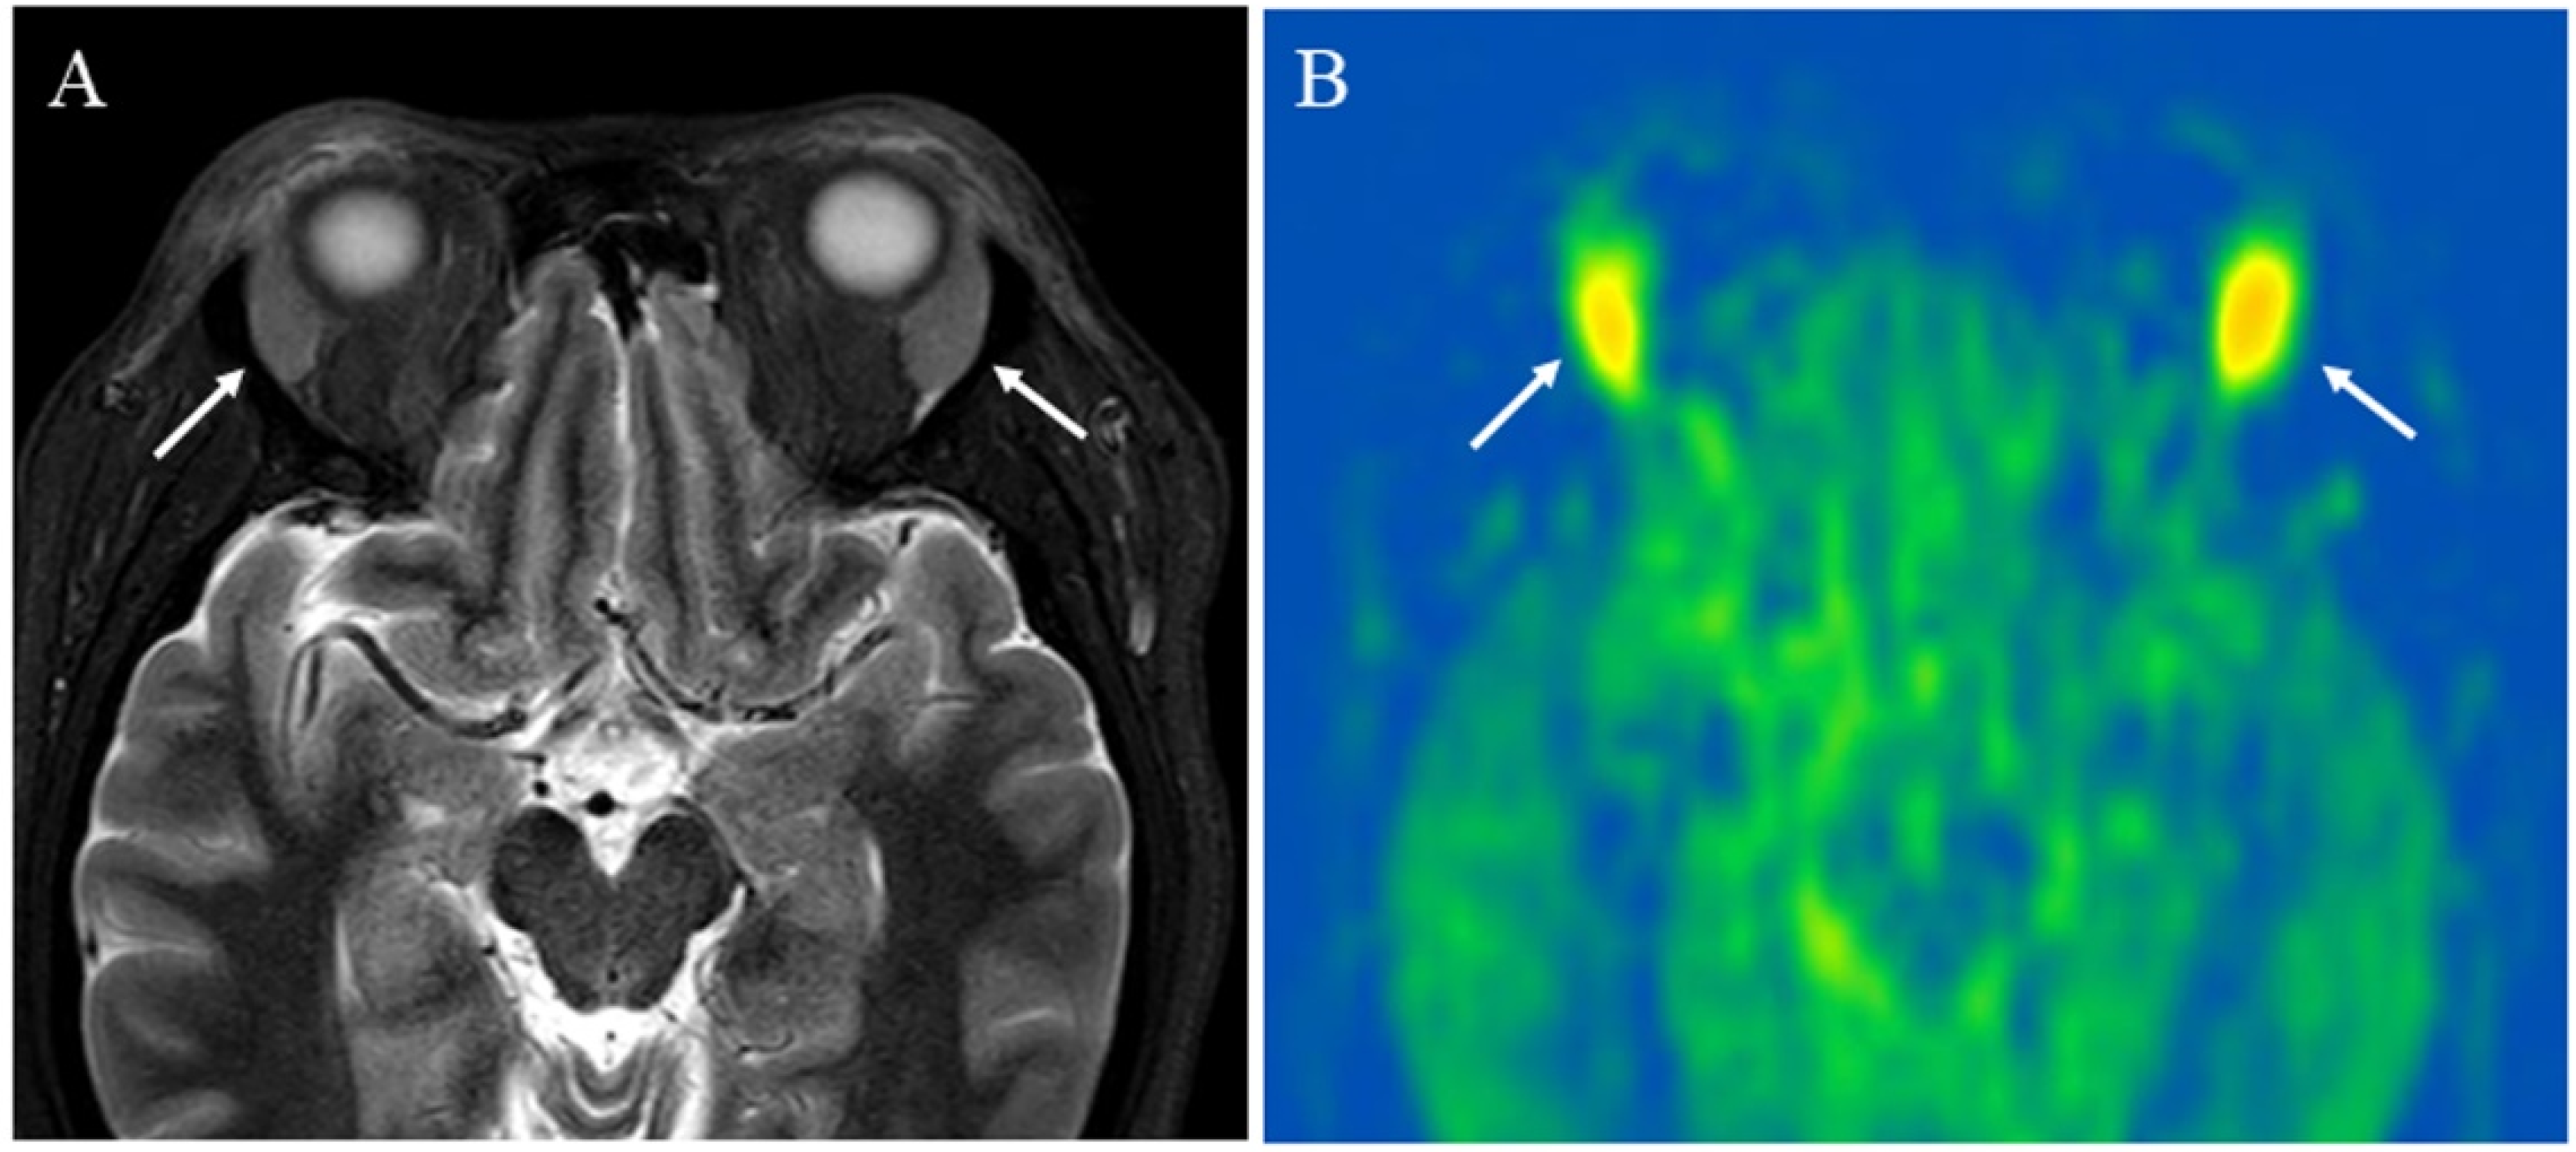

5.1.1. Inflammatory Lesions: Sialadenitis and Dacryoadenitis

5.1.2. Hypervascular Lesions

- Boulouis, G.; Dangouloff-Ros, V.; Boccara, O.; Garabedian, N.; Soupre, V.; Picard, A.; Couloigner, V.; Boddaert, N.; Naggara, O.; Brunelle, F. Arterial Spin-Labeling to Discriminate Pediatric Cervicofacial Soft-Tissue Vascular Anomalies. AJNR Am. J. Neuroradiol. 2017, 38, 633–638. [Google Scholar] [CrossRef]